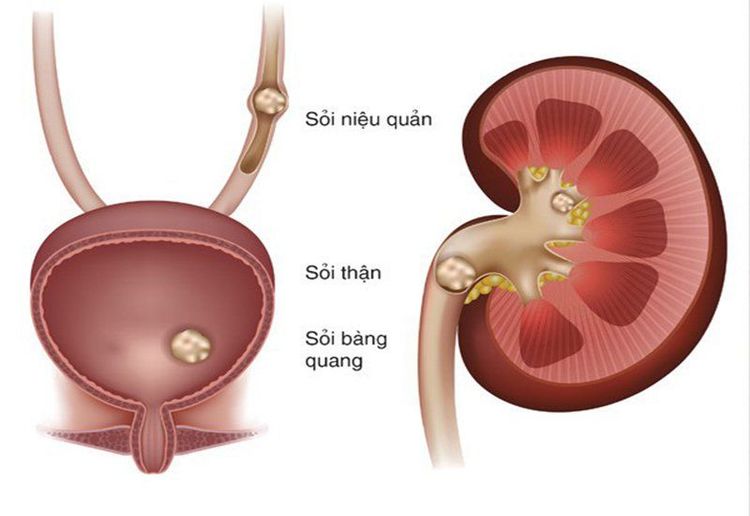

Bệnh xốp thận (Cacchi-Ricci) là một rối loạn bẩm sinh của thận, đặc trưng bởi tình trạng giãn nở các ống dẫn nước tiểu nhỏ ở 1 hoặc cả 2 thận. Trong thận của bệnh nhân bị xốp thận có các nang và có thể tồn tại sỏi trong các nang này. Các nang này tạo thành dạng xốp như miếng bọt biển, giữ nước tiểu chảy tự do trong các ống và trong thận. Người mắc bệnh xốp thận có nguy cơ cao bị sỏi thận và nhiễm trùng đường tiểu do ứ đọng nước tiểu. Bệnh nhân thường phải lọc sỏi thận mỗi năm. Dù vậy, bệnh xốp thận vẫn được coi là một rối loạn lành tính, có tỷ lệ mắc bệnh khá thấp.

Về triệu chứng, ở giai đoạn đầu bệnh xốp thận có thể không có triệu chứng. Dấu hiệu đầu tiên mà người bệnh thường gặp là nhiễm trùng đường tiểu hoặc sỏi thận. Các triệu chứng gây ra bởi 2 căn bệnh này gồm: Đau ở lưng, bụng dưới hoặc háng; buốt hoặc đau khi đi tiểu; nước tiểu có nhiều bọt, có màu tối hoặc lẫn máu; nước tiểu có mùi hôi thối; sốt và ớn lạnh; nôn mửa.

Gai thận là nơi các ống sinh niệu tập hợp nước tiểu lại và đổ vào đài thận nhỏ. Mỗi thận có khoảng 8 – 14 đài thận nhỏ, được sắp xếp thành 2 lớp. Bệnh hoại tử gai thận là do thiếu máu gai thận, thường gặp ở bệnh nhân tiểu đường, thường bị nặng thêm do nguyên nhân nhiễm trùng hoặc tắc nghẽn. Ngoài ra, việc uống quá nhiều thuốc giảm đau hoặc mắc bệnh hồng cầu hình liềm cũng có thể dẫn tới bệnh hoại tử gai thận.